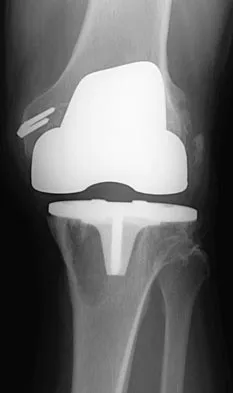

Which of the following findings is seen in the chest radiograph shown in Figure 13?

Explanation

Orthopaedic surgeons are often responsible for interpreting radiographs of general examinations such as the chest radiograph shown. For accurate interpretation, it is important to systematically review all of the information available on the radiograph. Using this approach, the fracture of the left proximal humerus is readily recognized. Linear air soft-tissue density at the lung periphery would suggest a pneumothorax, but this finding is not shown on the radiograph. The upper thoracic spine is well aligned. The sternoclavicular and distal clavicles are normal.